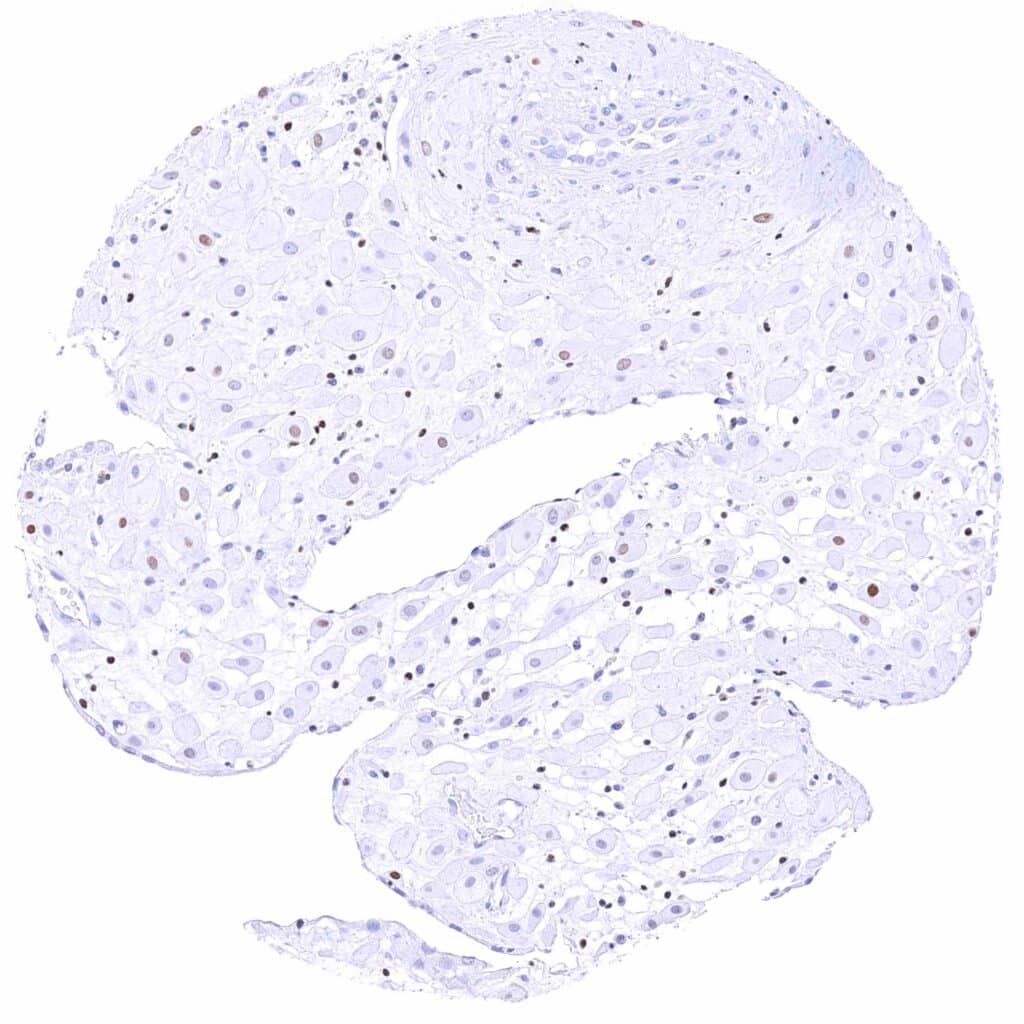

Prostate – Weak to moderate, nuclear GATA3 staining of basal cells. .jpeg